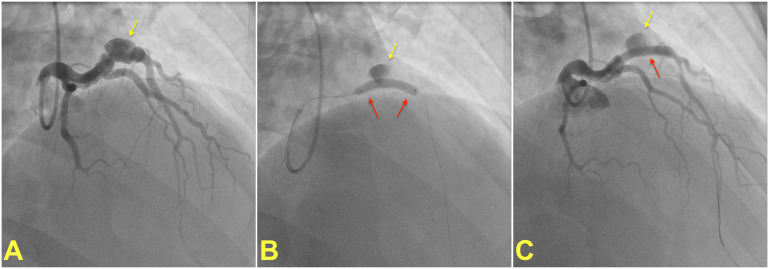

冠状动脉动脉瘤(CAAs)是常见的实体,高达8%的患者接受冠状动脉造影。CAAs最常见的病因是冠状动脉粥样硬化性“正性重塑”,同时先天性、炎症性和创伤性病因也可见。动脉瘤是血栓形成的中心,血栓可能阻塞动脉瘤段或远端栓塞。动脉瘤破裂是CAA的一种罕见但潜在的灾难性并发症。大多数动脉瘤可以通过药物治疗,而对于易于破裂或血栓形成的CAAs,经皮排除冠状动脉循环动脉瘤是合适的。手术矫正仍然是患者的最终选择谁不适合经皮管理或那些有令人信服的手术指征。本文综述了CAAs的命名、分类、病理生理学、诊断和管理方面的现有知识,并特别强调了减轻CAAs相关风险的治疗策略。

Coronary artery aneurysms (CAAs) are frequent entities that are encountered in up to 8% of patients undergoing coronary imaging. The most frequent cause of CAAs is atherosclerotic "positive remodeling" of coronary arteries, while congenital, inflammatory, and traumatic etiologies could also be seen. Aneurysms serve as foci for thrombus formation, which may occlude the aneurysmatic segment or embolize distally. Rupture of an aneurysm is a rare yet potentially catastrophic complication of a CAA. Most aneurysms can be managed medically, while percutaneous exclusion of an aneurysm from coronary circulation is appropriate for CAAs that are prone to rupture or thrombosis. Surgical correction remains the ultimate option for patients who are not amenable to percutaneous management or those with a compelling indication for surgery. This review summarizes the available knowledge on the nomenclature, classification, pathophysiology, diagnosis, and management of CAAs, with a particular emphasis on treatment strategies to mitigate the risks associated with CAAs.